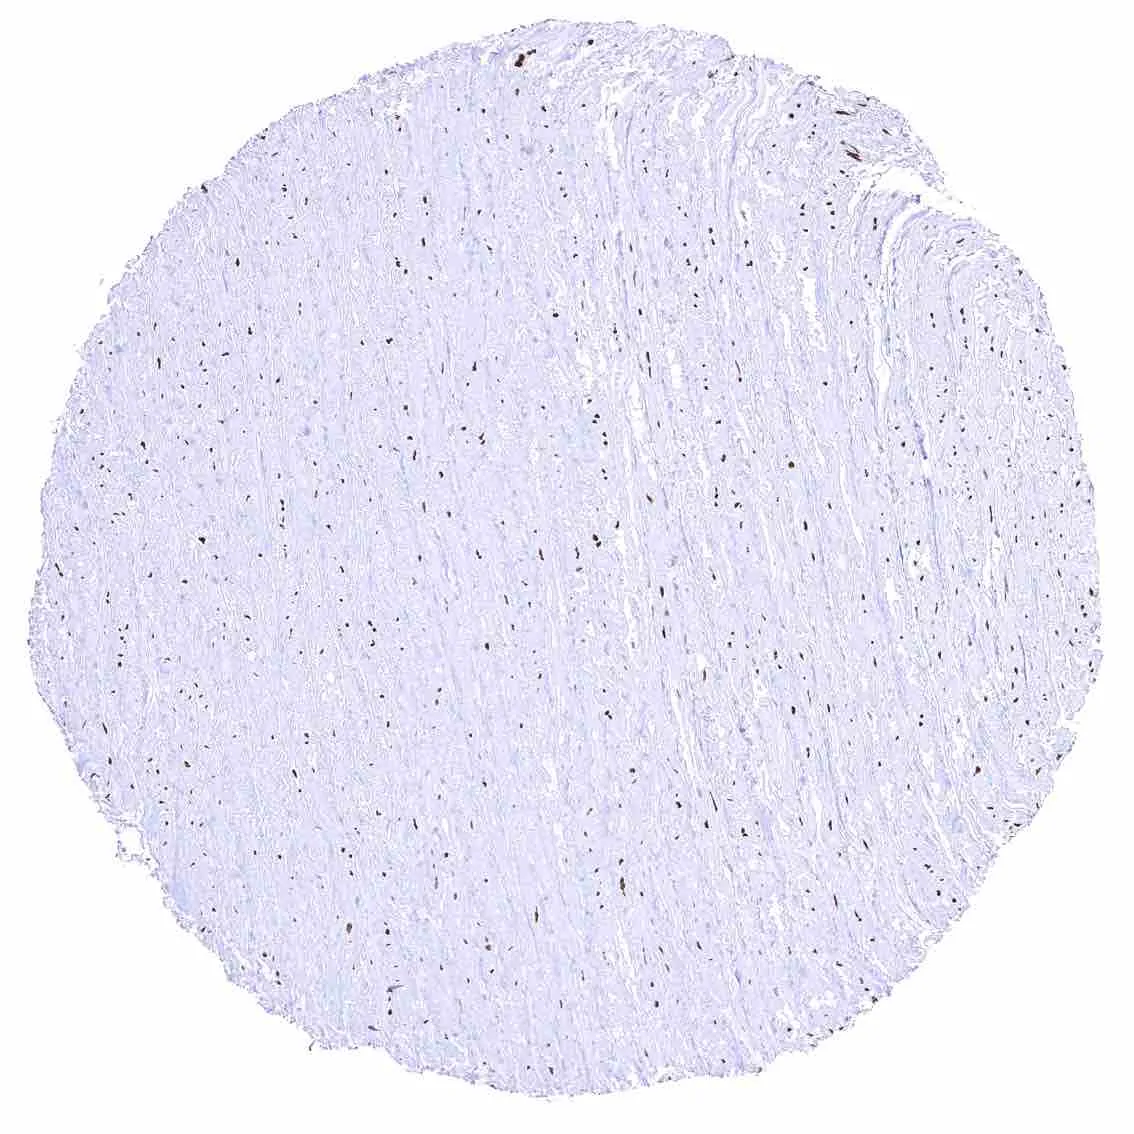

Urinary bladder, muscular wall